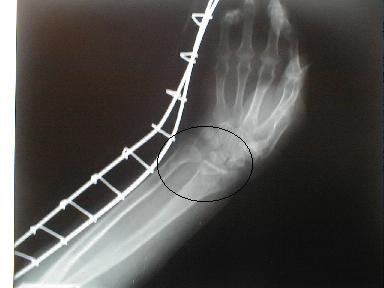

2月25日

3月25日

日常動作には支障なく経過良好にて治癒とする